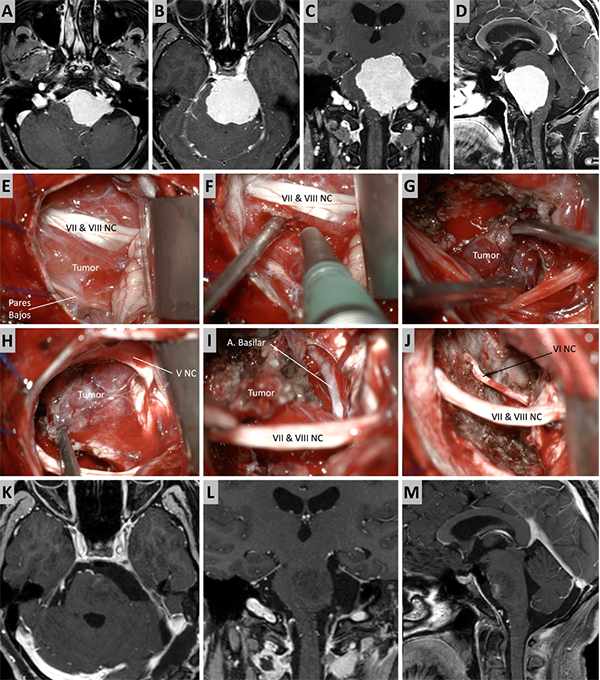

Figura 5. Caso ilustrativo #3. A-D. Resonancia que muestra MRPC con implantación clival. E-J. Se realiza un abordaje retrosigmoideo, consiguiendo la liberación del complejo VII-VIII del tumor y su resección completa. K-M. Resultado imagenológico postquirúrgico.